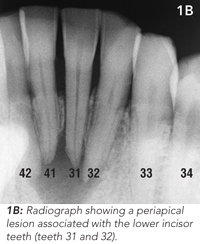

Routine clinical dental tests were conducted, including tooth percussion and CO2 dental pulp testing. Radiographic examination revealed a broad radiolucency associated with three of the lower incisor teeth (Figure 1B). These findings led to a diagnosis of chronic apical periodontitis caused by pulpal necrosis and infection of two lower incisor teeth (teeth 31 and 32). Tooth 41 was vital.